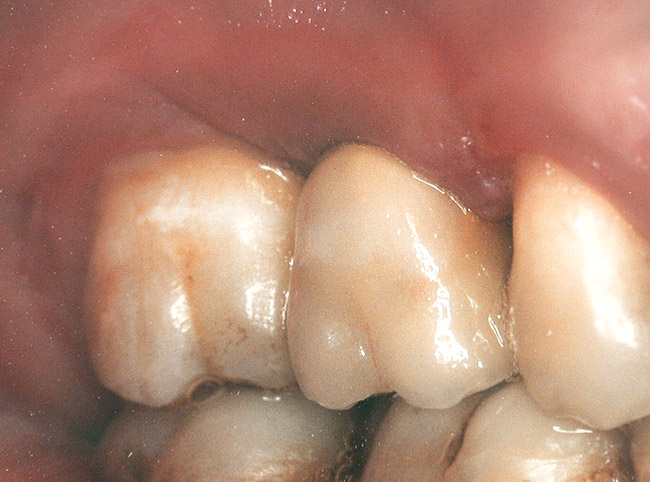

Second-stage surgery was performed after 5 months; healing abutments were placed, and the soft tissue was allowed to heal for an additional 5 weeks. Splinted porcelain-fused-to-metal (PFM) crowns supported by custom gold abutments then were delivered (Figure 5).

Figure 5  Final implant-supported PFM restorations.

Figure 5

Figure 9  Final implant-supported PFM restorations.

Figure 9